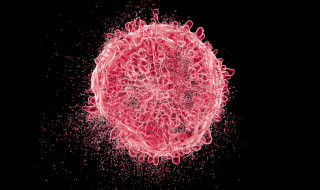

Viruses target men and women differently, research suggests

New research has shown that viral infections can evolve to affect men and women differently and become more virulent in…